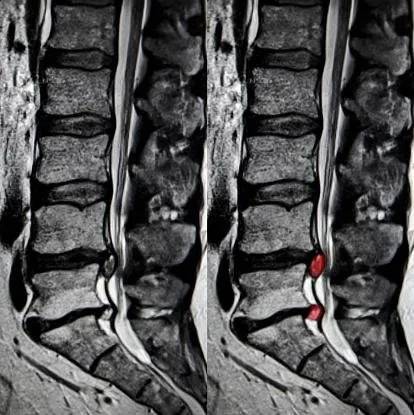

Tra le affezioni del sistema muscolo-scheletrico curabili attraverso l'ossigeno-ozonoterapia figura anche l’ernia del disco. Il trattamento consiste in delle microiniezioni in sede lombare o in sede cervicale, necessarie per alleviare il dolore e il recupero di una certa autonomia motoria e funzionale, per lo svolgimento di tutte le attività quotidiane.

Alla fine del ciclo di microiniezioni è utile eseguire degli esami strumentali, come la risonanza magnetica nucleare, per documentare una riduzione significativa dell’ernia. In seguito alla terapia, inoltre, è importante preservare i risultati raggiunti con uno stile di vita adeguato alla propria condizione psicofisica, una correzione posturale e una buona ergonomia lavorativa.